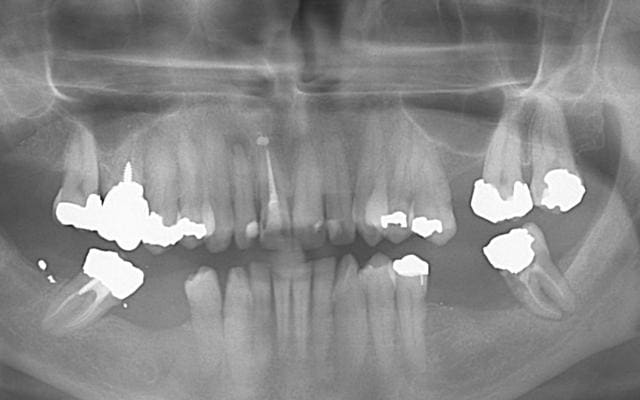

Je viens de voir cette patiente CMU ce matin.

Un confrère lui a expliqué que la 16 n'est pas conservable et qu'un bridge est à faire dans la foulée. La 17 n'est pas en contact de la 16...

La 37 n'est pas mobile mais est-elle conservable ??

Si une idée alternative pouvait apparaître pour conserver la 37 ou pour temporiser ....

Pour moi la 37 est perdue, et je suis étonné qu'elle ne soit pas mobile......mais je ne remet pas ton examen en doute.

J'ai vu cette patiente en urgence, ce matin. Son problème était le fait que la 16 ne soit pas conservable. Un IRM a été mis entre 16-17. Ce n'est pas la 16 qui m'a semblé bizarre mais la gencive en M de 37, d'ou la pano et la surprise.

37 mésiale

quelle est l'origine de cette lesion dentinaire ?

cf une radio par exemple 10-2006 parmi tant d'autre. Dent traitée pour une pulpite en 2005 sans cause flagrante. Radio prise pour faire une reconstitution prothétique. Lyse radiculaire M sous-gingivale. Palpation à la sonde : paroi dure et lisse

prions pour que la 16 soit conservable, seule la dépose de l'amalgame et du screw-poste permettra de l'établir

avant cela, avertir la patiente d'une éventuelle extraction extemporanée

dans le premier cas, reconstitition collée et coiffe

dans le deuxième, bio des 17 et 15 et bridge, avec les précautions oratoires d'usage et considérant que le cadre restrictif de la CMU, s'il est accepté par la patiente l'incline à accepter les bio et le supplément pour l'inter

en bas, dans la même optique CMU réel, càd sans bézef de tunes: reconstitution des, 37 après hémisection, 47, coiffes fraisées, stellite (la prémolaire avec ancrage intradentiainre serait avantageusement coiffée)

les reprises de traitements endodontiques, celui de la 12 nécrosée, et la reprise des amalgames débordants ou infiltrés étant bien sûr sous-entendus.

tout à fait ok avec ton observation et pour revenir au cas de la 37 je pense qu"elle est condamnée et que la lesion mesiale n'est pas de la carie mais "resorbtive" origine des cellules grignoteuses??desmodonte?pulpe?

j'ai essayé de traiter une dent qui ressemblait à celle ci et malgré la reprise du trt racine l'inlay core et la cr la resorbtion à continuée et tt a foiré